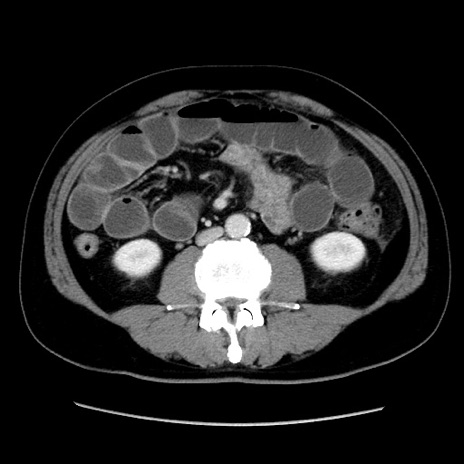

症例16(横断像)

【症例】 70歳代男性

【主訴】 腹痛、嘔吐

【現病歴】 約1ヶ月前より間欠的に腹痛と嘔吐あり、当院消化器内科を受診したところCTで多発する肝臓のLDAを指摘され、精査中であった。以降は消化器症状は安定していたが、2日前より嘔気と腹痛があり、同日より排便・排ガスが消失した。改善認めず、 本日、救急外来を受診した。

【既往歴】 大腸ポリープ切除後。

【身体所見】意識清明・会話良好、BT 36.3℃、BP 127/80mmHg、 P 80bpm、腹部:膨満あり、平坦・軟、上腹部正中および下腹部正中に圧痛あり、反跳痛なし、筋性防御なし。

【データ】WBC 7200、CRP 0.77